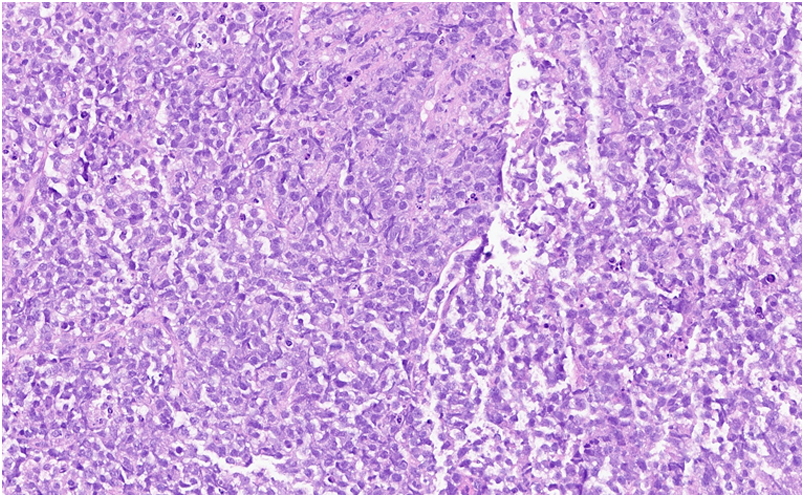

Figure 3

Hematoxylin and eosin stain: large lymphocytes cells with moderately abundant cytoplasm and oval nuclei containing several nucleoli corresponding to centroblasts.

In March 2022, a 63-year-old man without notable past medical history presented with rapidly progressive exertional dyspnea associated with night sweats. The electrocardiogram revealed complete atrioventricular block (AVB) with a heart rate of 40 beats per minutes and narrow QRS complexes. Lab tests showed anemia with hemoglobin at 9 g/dl, normal renal function and a biological inflammatory syndrome with CRP at 181 mg/L (normal upper limit: 4 mg/L) and the patient was transferred to the intensive care unit with Isoprenaline infusion. The initial workup included a bedside transthoracic echocardiography, which revealed a heterogeneous left atrial mass, measured at 50 × 60 mm, infiltrating the inter-atrial septum with an extension into the right atrium measured at 43 × 26 mm. This mass seemed to be implanted in the lateral wall of the left atrium and prolapsed into the mitral valve causing moderate mitral regurgitation and significant mitral stenosis with a mean gradient ranging from 7 to 14 mmHg. Then, a thoracic, abdominal and pelvic CT scan was performed and showed the cardiac mass associated with a mild pericardial effusion, hilar and mediastinal lymphadenopathy and bilateral moderate pleural effusion (Figure 1). The workup was completed by a cardiac magnetic resonance imaging (CMR) study to better characterize the mass. CMR confirmed the presence of a bulky mass with a “cauliflower” appearance, extending throughout the entire left atrium, infiltrating the interatrial septum and the right atrium as well as the basal inferior and inferolateral walls of the left ventricle (Figure 2A). This mass appeared isointense on black blood spin echo T1-weighted imaging, slightly hyperintense on fat saturated T2-weighted imaging with a heterogeneous enhancement on late gadolinium enhancement (LGE) sequences (Figures 2B,C), suggestive of a malignant tumor. In order to distinguish between cardiac lymphoma or sarcoma, for which initial treatments are diametrically opposed (i.e., urgent chemotherapy vs. surgical resection) (1), a myocardial biopsy guided by transesophageal echocardiography was performed. Four endomyocardial fragments were collected from the right atrial side of the interatrial septum via a femoral venous access. Given the persistence of complete AVB at day 7, a VVI single lead transvenous pacemaker was implanted. Prompt pathological analysis revealed the presence of a diffuse large B-cell lymphoma classified as germinal center B cell type (CD10+, BCL6+, MUM1+), with a double expression of MYC/BCL2 (Figure 3). Urgent treatment was initiated as soon as the pathology results were obtained, 10 days after the biopsy, with corticosteroids (1 mg/kg) associated with chemotherapy including rituximab, cyclophosphamide, doxorubicin, vincristine, and prednisone (R-CHOP). Six cycles of R-CHOP were completed within 6 months, allowing a clear improvement of the dyspnea and of the overall condition. CT-scan after the fourth cycle of R-CHOP showed complete remission of the lymphoma (2). After setting the MR conditional pacemaker to DOO mode, follow-up CMR revealed complete disappearance of the cardiac mass (Figures 2D–F). Because the patient was in spontaneous sinus rhythm at the last visit and the stimulation rate dropped from 100% to 26% after the third R-CHOP cycle, an evaluation by the cardiac electrophysiologist was scheduled 3 months later to assess the percentage of RV pacing for possible pacemaker removal. Written informed consent was obtained from the patient for the publication of any potentially identifiable images or data included in this article.